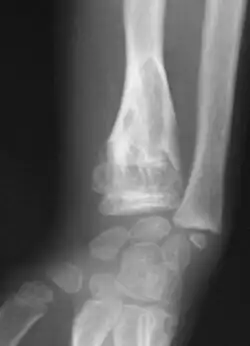

-

Enchondromas localized in the upper part of the humerus of the same patient